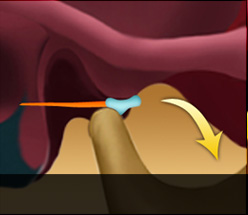

턱관절 디스크가 정상위치보다 앞으로 나와있는 상태입니다. 얼굴뼈와 턱뼈 사이에서 윤활작용을 해야 할 디스크가 앞으로 빠져있기 때문에 입이 잘 벌어지지 않고 입을 벌릴 때 통증을 느끼게 됩니다. 입을 크게 열면 앞으로 빠져있던 디스크가 턱뼈에 걸려 제자리로 돌아가며 ‘딱’하고 소리가 나는 경우와 입을 아무리 벌려도 디스크가 제자리로 돌아가지 못해 소리조차 나지 않는 경우로 나눌 수 있습니다. 얼굴의 근육과 인대 손상은 물론 목의 이상까지 동반하는 경우가 많기 때문에 수개월 이상의 치료가 필요한 경우가 대부분입니다.

디스크 전방전위1

입을 다물고 있는 상태

입을 열고 있는 상태

입을 열면 디스크가 제자리로

돌아가는 경우

디스크 전방전위2

입을 다물고 있는 상태

입을 열고 있는 상태

입을 열어도 디스크가 제자리로

돌아가지 못하는 경우